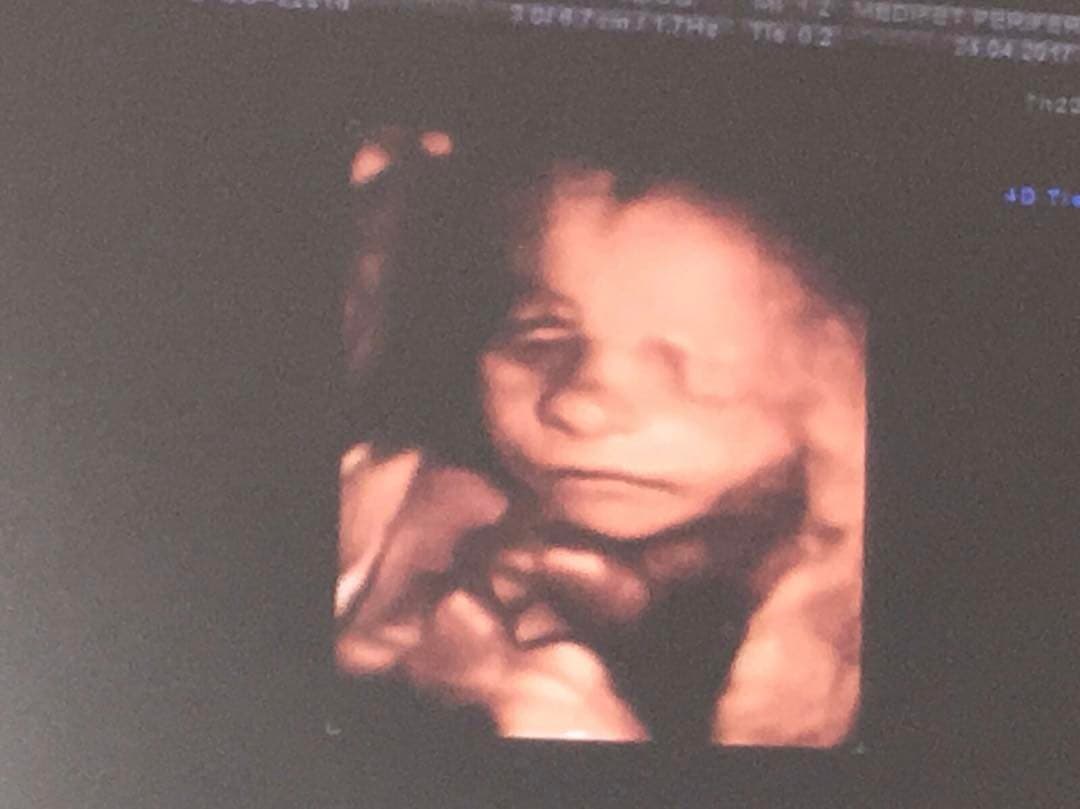

Esta fue la primera imagen del ultrasonido que compartió la actriz del pequeño Mariano, y sin ocultar su enorme felicidad le dio las gracias a su esposo e hijo por el apoyo en esta nueva etapa.